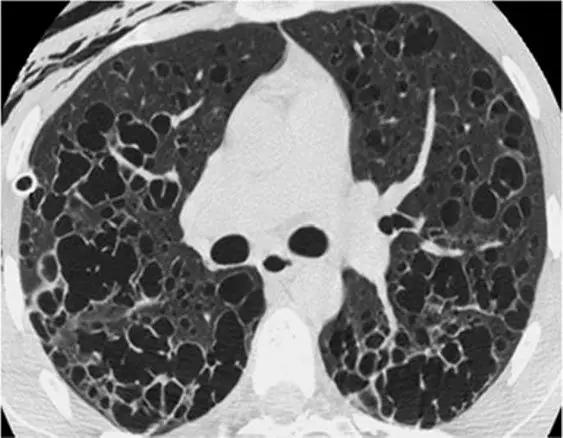

8、囊性病变

囊性模式由界限分明,圆形和外接空气的实质组成,有界限分明的壁和与正常肺。

经典疾病:淋巴管平滑肌肌瘤病(LAM),其特征是通常存在圆形的薄壁肺囊肿,没有在局部明显的特点,分布广泛,包括肋骨角和肺底。 LAM可能伴有胸水表现为胸膜胸腔积液。鉴别诊断是随机分布的囊肿,临床病史表现几乎只影响着育龄妇女。鉴别疾病:是肺组织细胞增生症、淋巴细胞性间质性肺炎(LIP)和小叶性肺气肿。

*LAM。上叶水平的HRCT表现出“囊性模式”,其特征是位于肺实质和隔中的许多大小不等的薄壁“真”囊腔的存在。

肺组织细胞增生症在处于纯囊性期(纯结节性和结节性-囊性期之后的第三期)时模拟LAM。它的特征是存在薄壁和厚壁的囊、形状呈异形,类似于苜蓿叶。囊肿具有特征性以上部和中部肺区分布为主。

*组织细胞增多症。上叶水平的HRCT揭示了一种“囊肿型”,其特征是许多薄或厚的“真”囊肿,形状奇异,大小不一。在右胸膜腔中发现引流导管以治疗气胸,这是这位27岁重度吸烟患者。

淋巴细胞性间质性肺炎 (LIP)可能很少以弥散性肺囊肿为主要HRCT模式(图37)。鉴别诊断中支持LIP的主要发现是与其他辅助发现相关,例如磨玻璃样不透明的弥散性或斑片状区域,不明确的小叶小结节和支气管血管束增厚。此外,引起某种程度的免疫抑制的原发性疾病的临床病史(如干燥病,艾滋病,自身免疫性疾病,蛋白异常)为LIP提供了强有力的线索。

*淋巴细胞性间质性肺炎。上叶水平的HRCT揭示了一种“囊性模式”,其特征是极少的薄壁“真”囊肿,可能具有圆形或更多的分叶形状。免疫抑制的历史(艾滋病,干燥综合征,自身免疫性疾病,蛋白异常)有利于LIP的特异性诊断

小叶中心性肺气肿虽然不存在“真正的”囊,但有时可能会模仿由囊性表现的其他间质性肺疾病。

*中央小叶气肿。HRCT显示在大多数情况下,放射状的小叶中心区没有可辨认的壁(除了小叶间间隔增厚的区域),并且有一个中心白点(在放射线的中心)代表中心小叶动脉(白色箭头) )。中央小叶肺气肿偶发间质性疾病,表现为“真正的囊性病变” 。